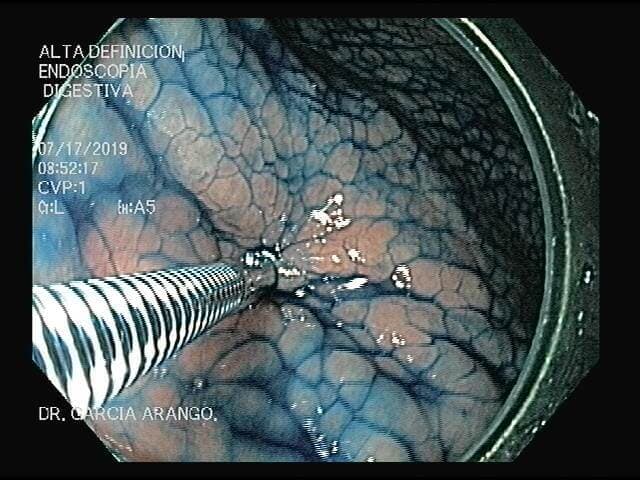

ENDOSCOPIA DIAGNÓSTICA Y TERAPÉUTICA AVANZADA CON ALTA DEFINICIÓN

⚕ Endoscopia de alta definición

⚕ Videoendoscopia y biopsias

⚕ Videocolonoscopia